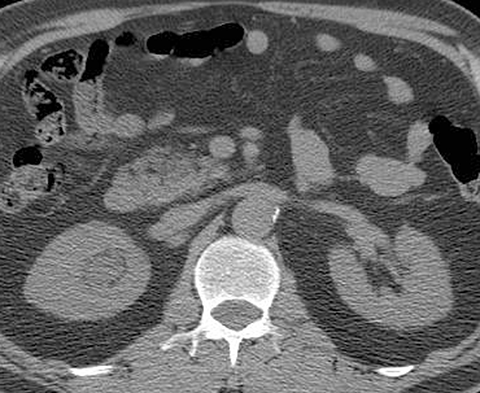

65-year-old male with painless hematuria [1 of 5]